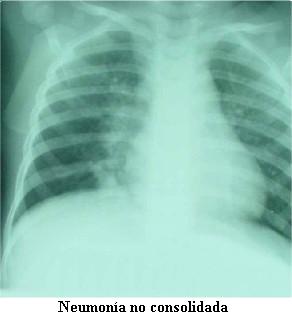

Estudios de base poblacional sobre la neumonía del niño adquirida en la comunidad son escasos en América latina y la epidemiología de S pneumoniae está pobremente establecida debido a la baja sensibilidad de las técnicas bacteriológicas. Para subsanar esas limitaciones la Organización Mundial de la Salud recomendó la interpretación estandarizada de las radiografías de tórax de los niños como una herramienta epidemiológica idónea para proporcionar datos sobre la carga de enfermedad que representan las neumonías bacterianas. Para ese propósito OMS/CDC propuso un protocolo genérico que fue adoptado en Uruguay.

Sse llevó a cabo tres años de vigilancia en cuatro hospitales de ambos departamentos cubriendo 229.128 habitantes, de los cuales 10,2% son menores de 5 años. A cada paciente hospitalizado se le realizó una historia clínica padronizada y se obtuvo una fotografía digital de la radiografía de tórax. Un pediatra y un radiólogo pediatra, con prescindencia de la historia clínica, interpretaron las imágenes digitales que a su vez fueron evaluadas por una comisión internacional de expertos. La etiología bacteriana y viral fue investigada.

De 2.184 pacientes captados, se dispuso para el análisis de 93,1% de las historias clínicas y las fotografías digitales. Según la interpretación radiográfica, 826 (40,6%) fueron neumonías consolidantes, 941 (46,3%) neumonías no consolidantes y 267 no fueron neumonías (13,1%). Los niños menores de dos años de edad predominaron (66,9%), de los cuales 45,8% tuvieron neumonías consolidantes. La tasa de incidencia anual de neumonía consolidante en los niños hospitalizados menores de cinco años fue 1.152 x 105, pero las tasas más altas se registraron en los pacientes menores de dos años.